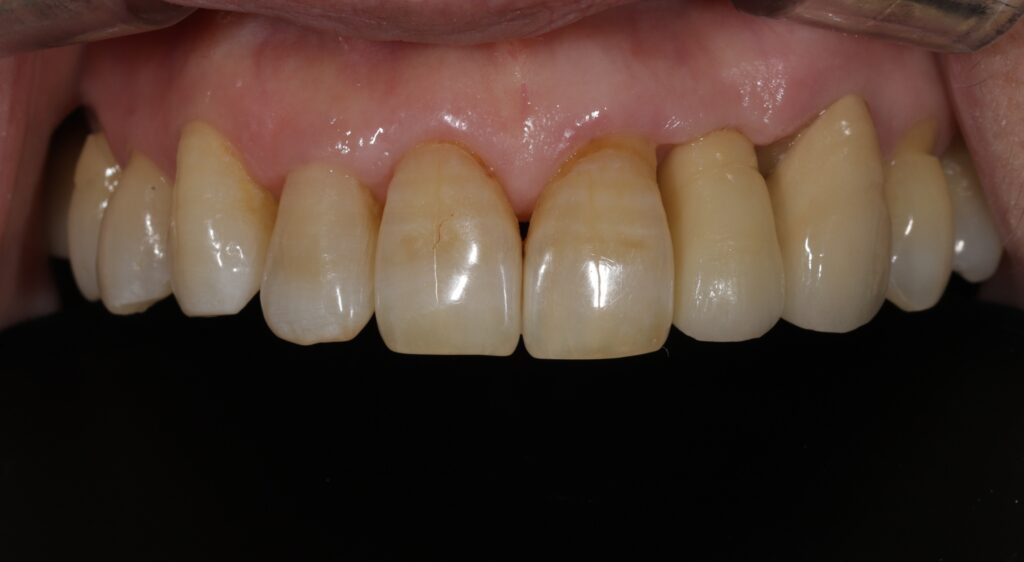

환자분께서는 벌어진 앞니 틈이 보기 싫어

치료 상담을 위해 을지로치과에 내원해 주셨습니다.

이미 상실한 위쪽 앞니와 아래쪽 앞니의 벌어진

틈도 치료를 원하셨는데요.

따라서 위쪽 앞니는 임플란트 식립과

아래쪽 앞니는 레진을 통해 틈을 메우는

치료를 진행하기로 하였습니다.